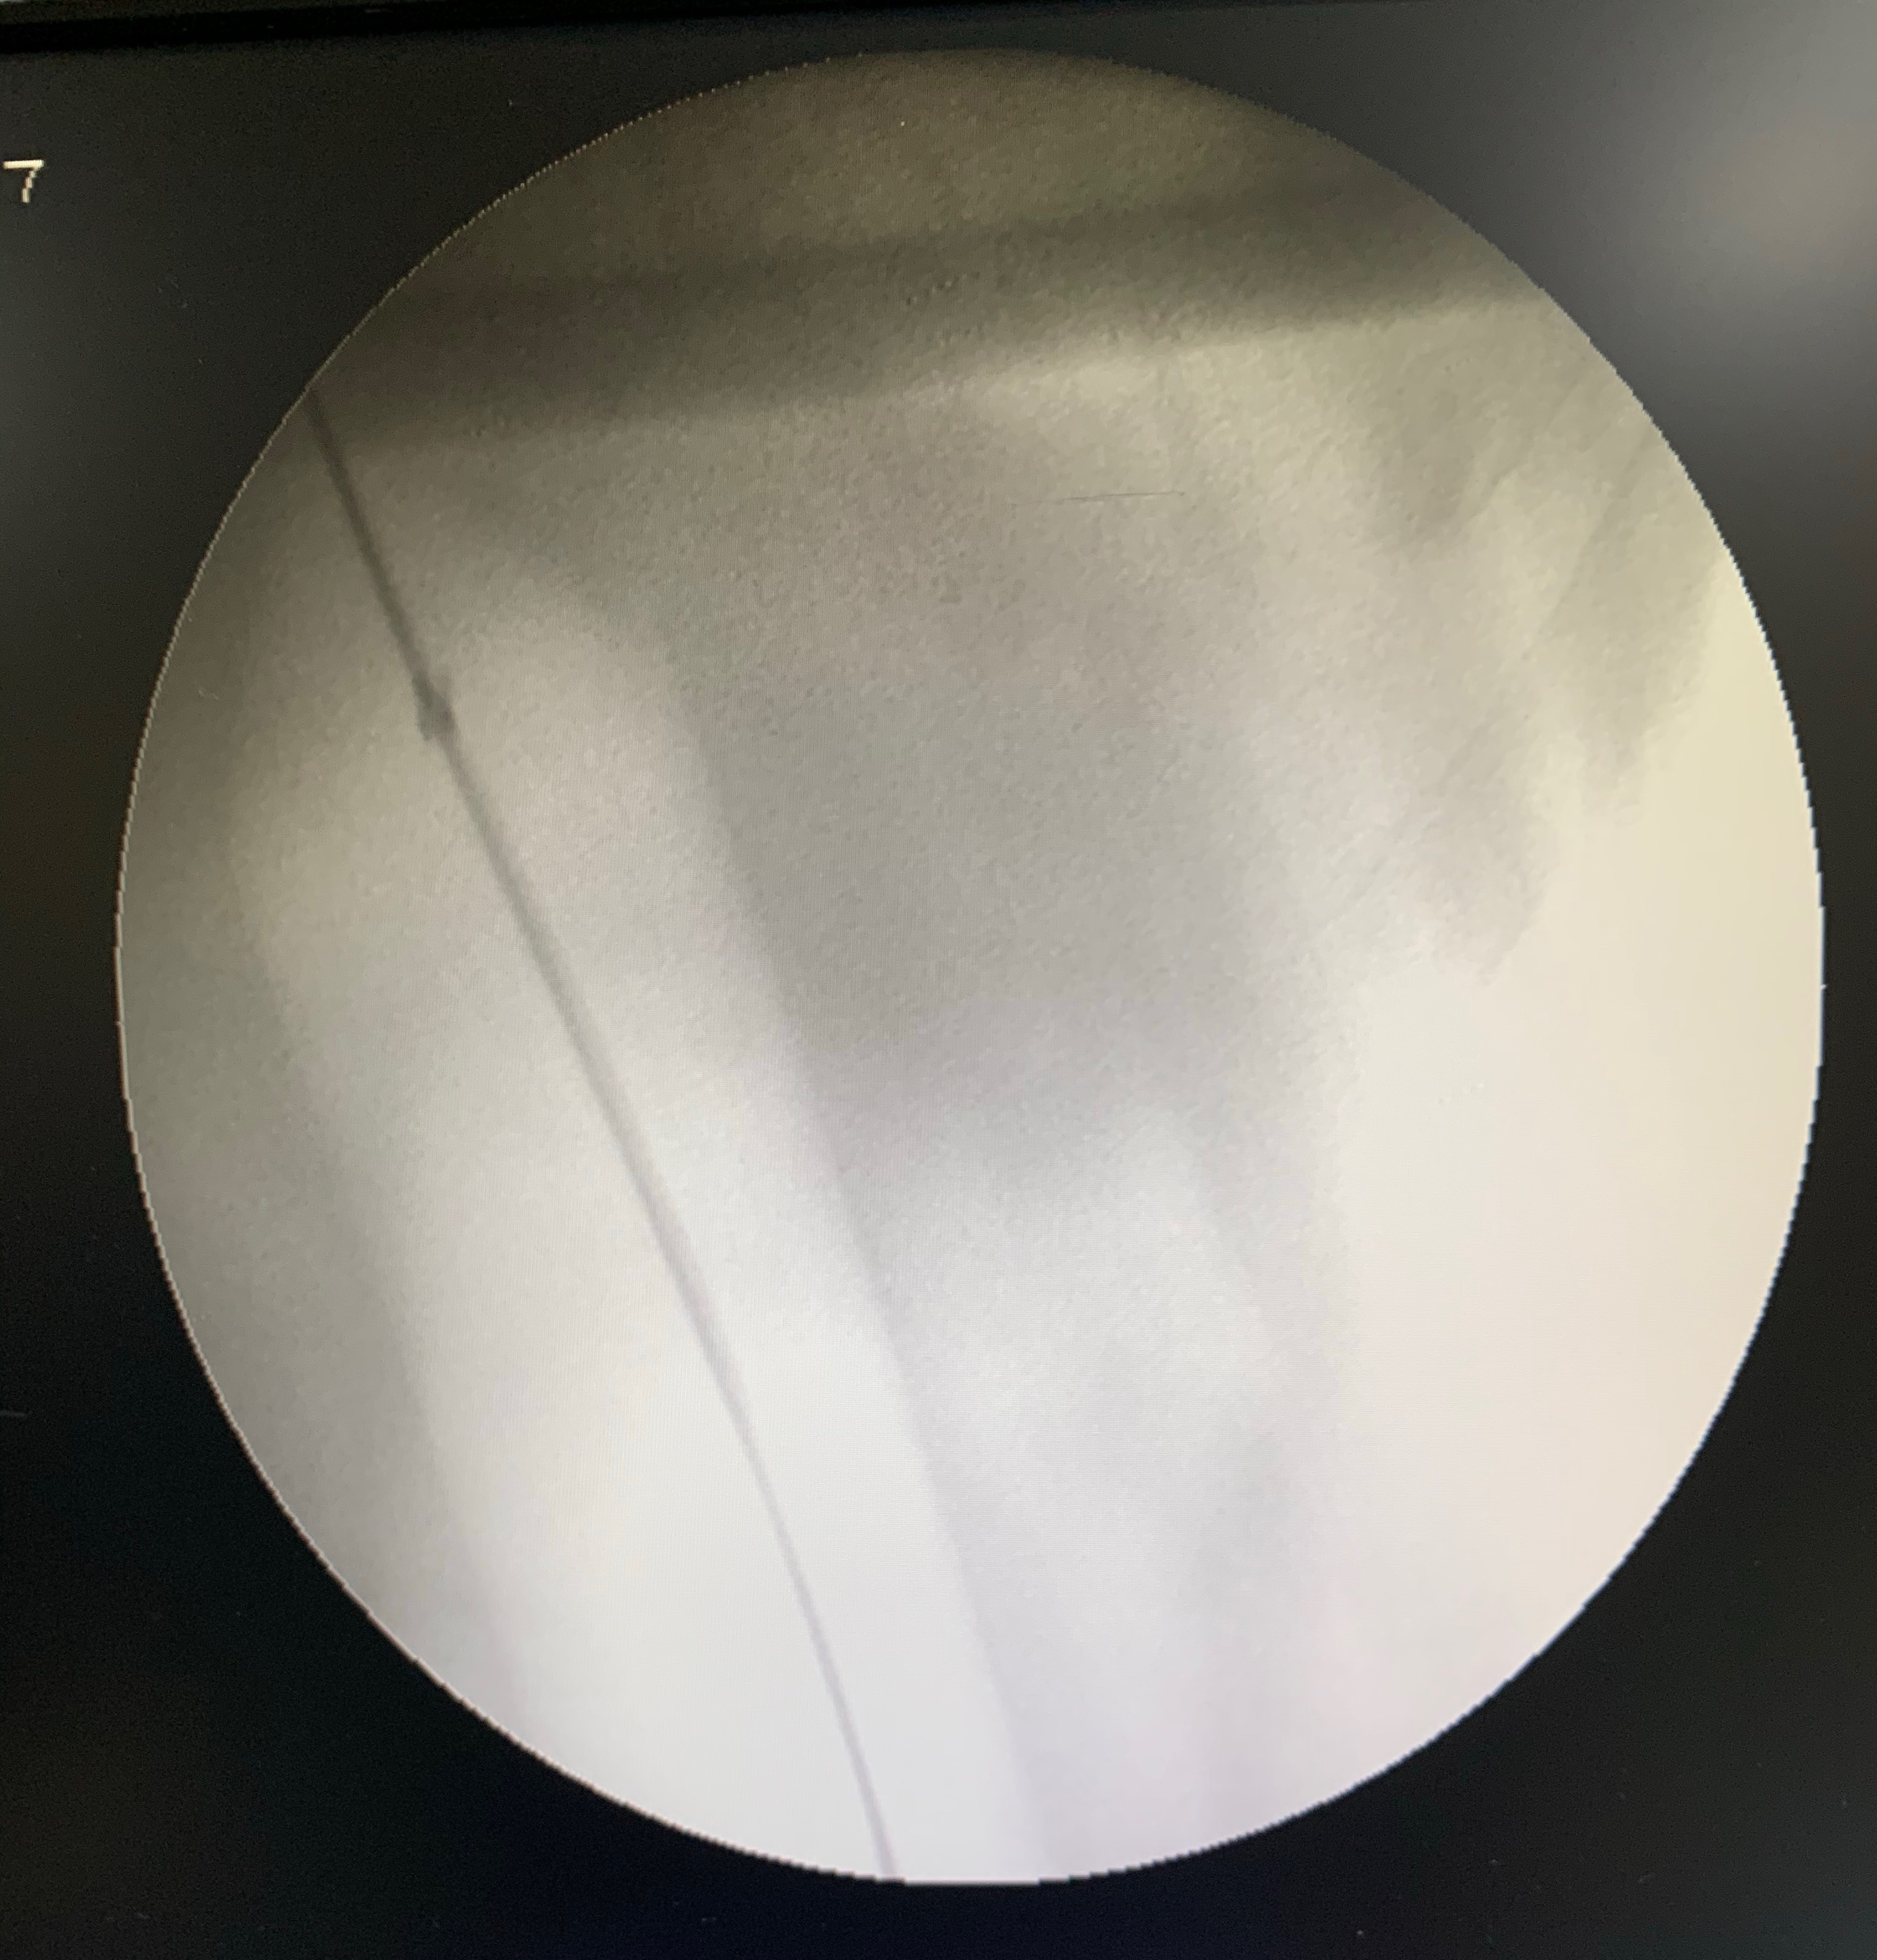

I pass a guide wire through the scope and withdraw the scope out of the body, leaving the wire in the stomach and comfortably across the cardia. Next, I pass a sophisticated device called an endoscopic balloon dilator over the wire and place it halfway in the esophagus and halfway in the stomach, confirming it’s position with a live x ray beam using a machine popularly known as “c-arm”.

The next step is to inflate the balloon at a specific pressure to dilate the cardia. This is quite a delicate task: too less inflation means a failed procedure and too much can tear the esophagus, causing torrential bleeding or a life threatening perforation.